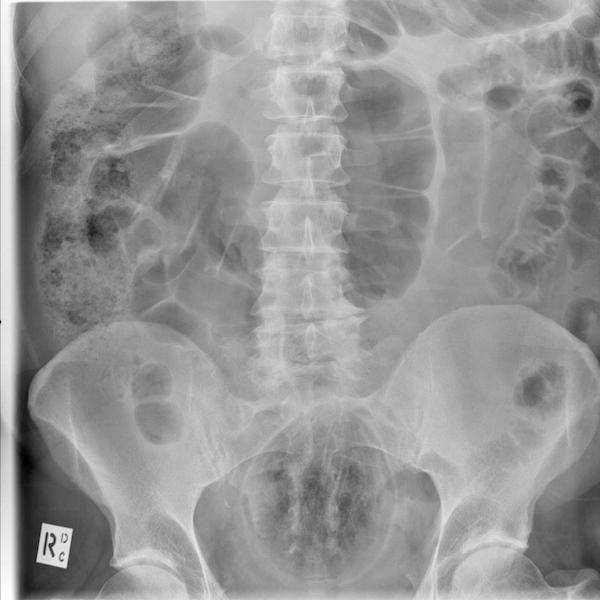

On suorastaan käsittämätöntä katsoa millaisia esineitä ihmiset nielevät ja tunkevat alapään kautta sisään. Röntgenosastolla työskentelevillä lääkäreillä on varmasti aika ajoin naurussa pidättelemistä, kun he löytävät alapäästä viinipulloja, kesäkurpitsoja ja jopa munakoisoja! Ihmiset ovat todella erikoisia varsinkin silloin, kun he yrittävät tyydyttää halunsa. Mukana on myös kuvia tapauksista, jotka sattuivat täysin vahingossa.#1 Naisen vatsasta löytyi 78 ruokailuvälinettä